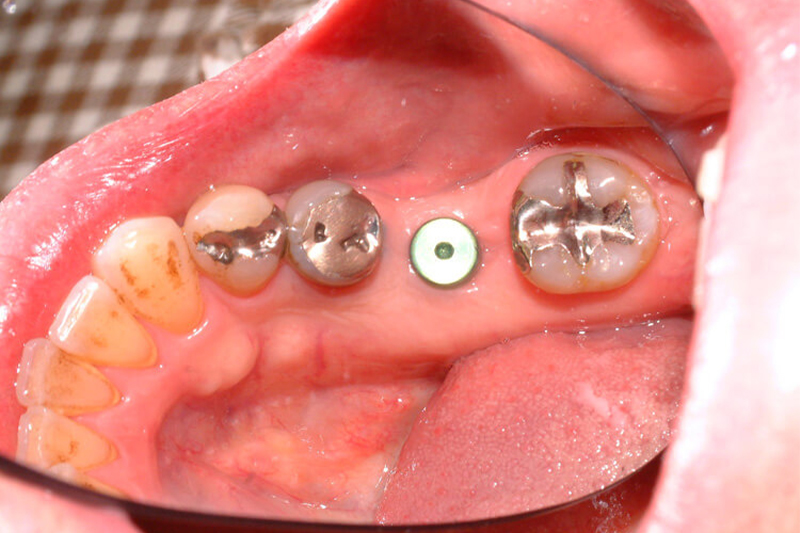

インプラントとは

失ってしまった自分の歯の代わりに、人工の歯根(フィクスチャー)を顎の骨に埋め込み、その上に人工の歯(上部構造)を作製して咬み合わせを回復する治療法です。固定性であるためガタついたりせず、自分の歯のように咬めるようになります。

フィクスチャー埋入の手術

歯の根に相当するインプラントの部品(=フィクスチャー)を手術により顎の骨に埋入する手術をおこないます。このフィクスチャー埋入の手術を白鳥インプラントセンター長白鳥清人先生におこなっていただきます。局部麻酔・静脈鎮静麻酔を用いておこないますので安心して手術を受けることができます。

STEP04

人工歯の装置

インプラントを含めた口腔全体の印象採得(=型をとること)をおこないます。インプラントの印象採得もiTero element 5Dを使用します。その型に従い人工の歯(上部構造)を作製します。その後、フィクスチャーに上部構造を装着して完成です。上部構造の作製はみと歯科・矯正歯科にておこないます。